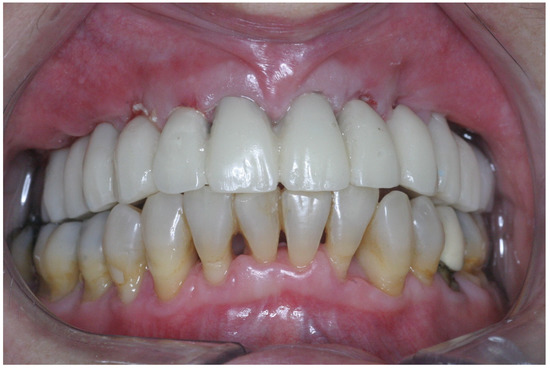

2.3. Prosthetic Protocol